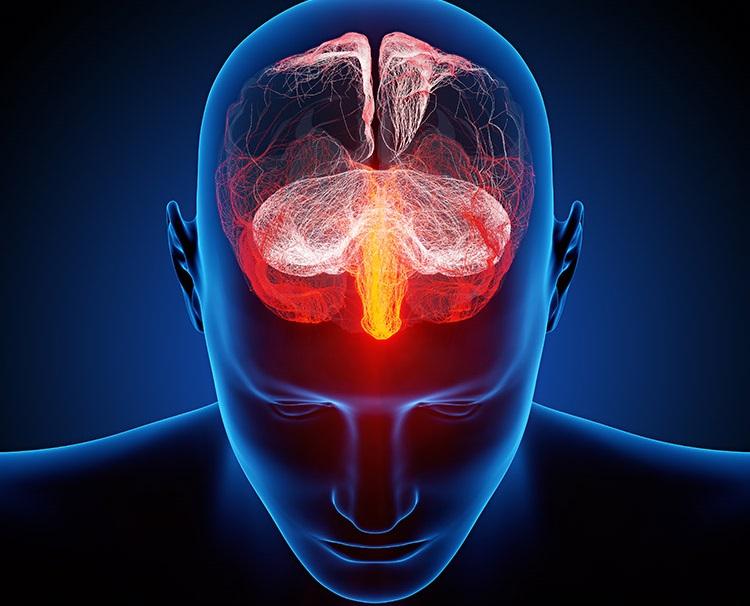

A esquizofrenia é um transtorno mental crônico caracterizado por distorções na percepção, pensamento, emoções e comportamento. Este artigo explora a diferença entre sintomas positivos e negativos da esquizofrenia, seus impactos na vida dos pacientes e apresenta as abordagens terapêuticas mais recentes para manejo e reabilitação.

A esquizofrenia afeta aproximadamente 1% da população mundial e é um dos transtornos psiquiátricos mais incapacitantes. Entender a divisão entre sintomas positivos e negativos é fundamental para o diagnóstico adequado e para a implementação de estratégias terapêuticas eficazes.

4.4 Estimulação Magnética Transcraniana (EMT)

A EMT é uma técnica promissora para o tratamento de sintomas negativos resistentes, modulando áreas específicas do cérebro.